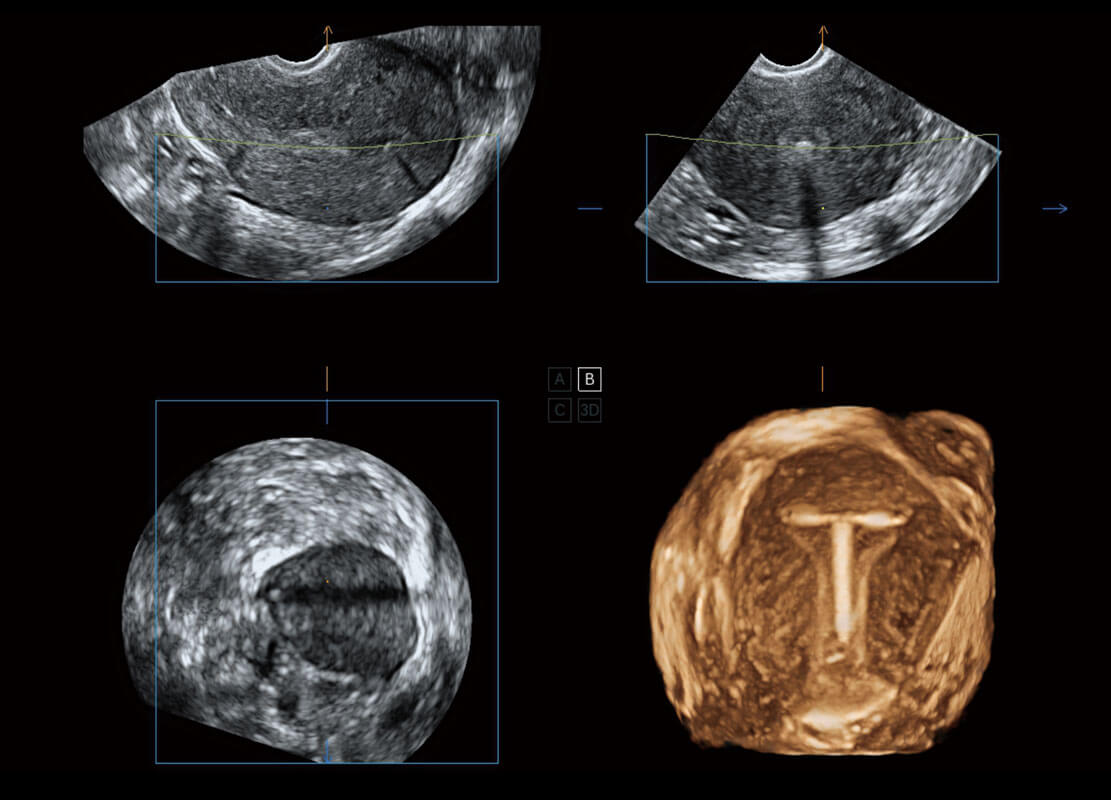

右室双出口

胎心容积成像